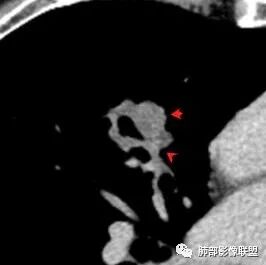

深分叶,部分边缘膨隆,也有部分平直

边缘光滑

部分边缘有短毛刺

我需要看这个是不是近端支气管堵塞,如果近端支气管明确,我就高度怀疑癌

空泡征